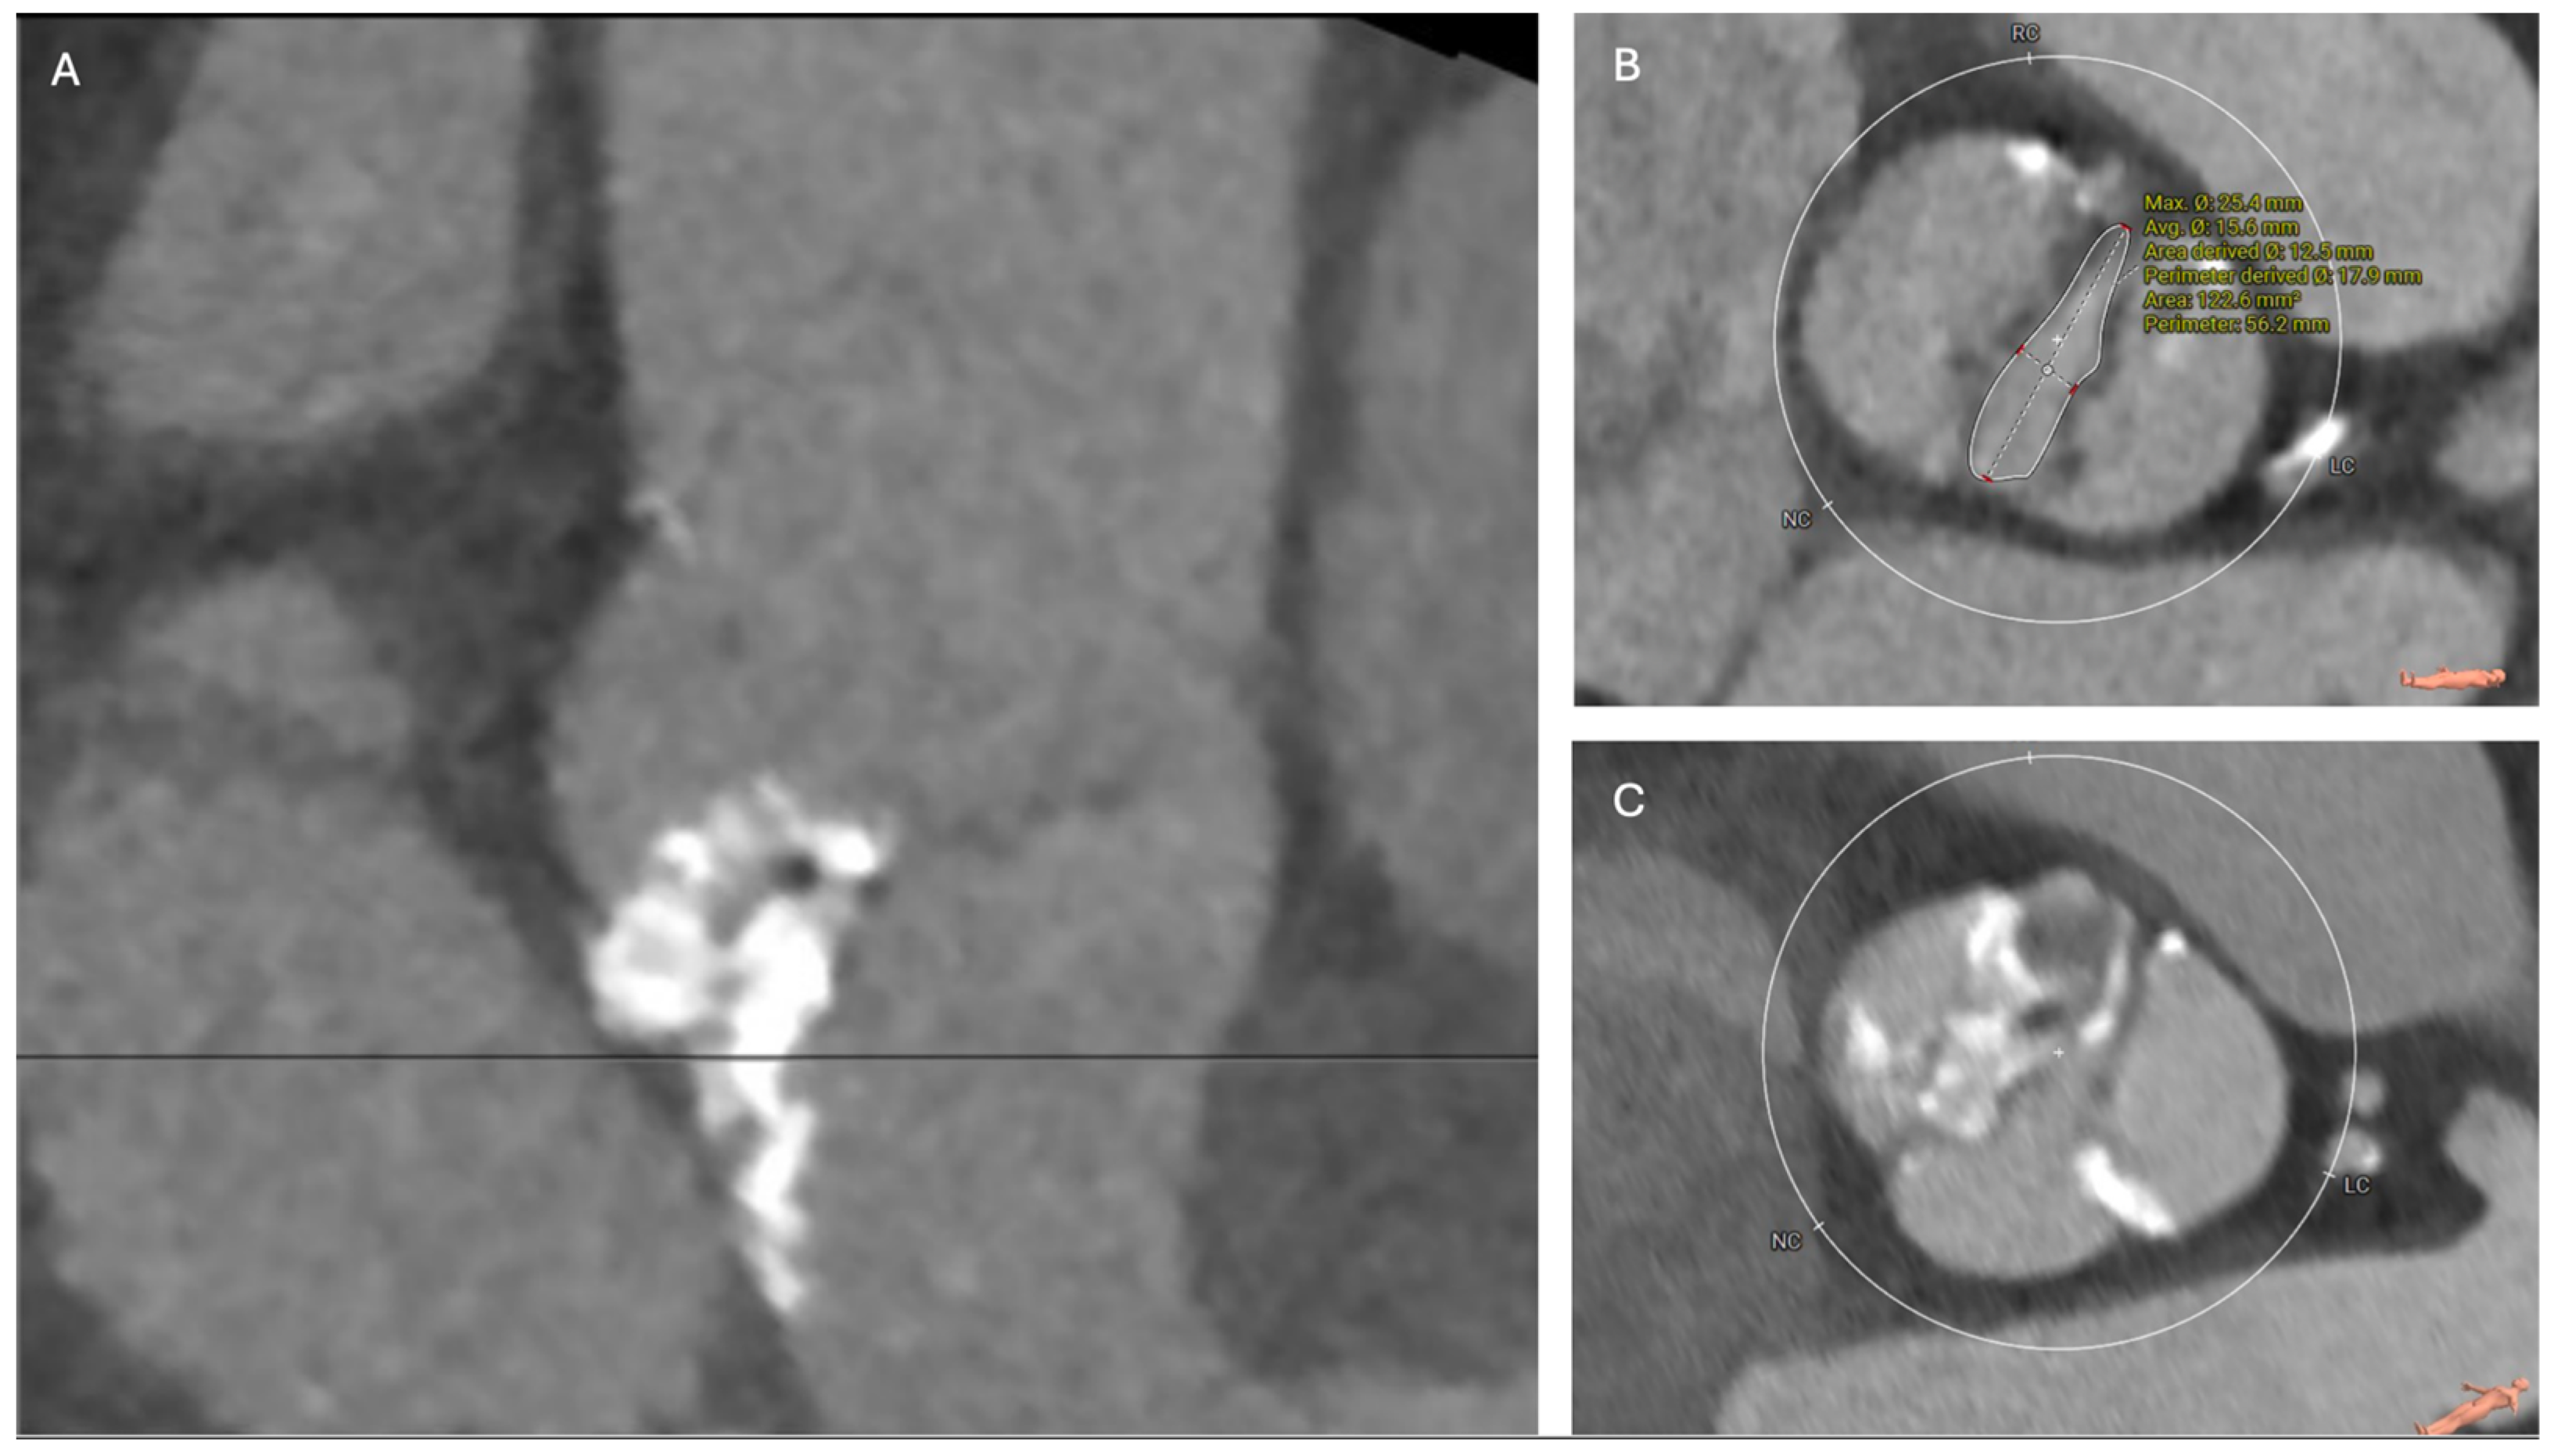

1.1. Anatomy